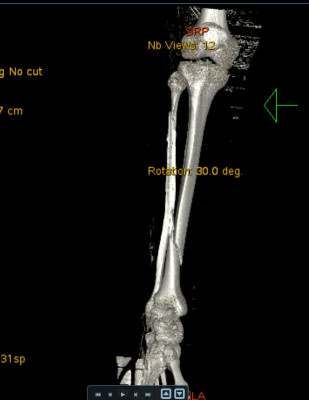

Bij deze mijn ervaring van 9 okt 2025